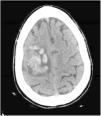

Cerebral thrombosis as a manifestation of poor control in inflammatory bowel disease

Figures (1)